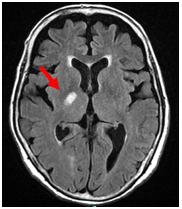

【アテローム血栓性脳梗塞】

動脈硬化により血管が狭くなっていき、狭くなった血管内腔の壁は不整なため血液中の血小板がこびりつき、さらに狭くなっていき最後は閉塞に至るものです。多くは高血圧、糖尿病、高脂血症などの生活習慣病が原因となります。徐々に詰まっていくことが多く、側副血行といって脇道から血流が補ってくれていることがあり、まだら状の大きな梗塞を呈することが多いです。

MRI

【MRA】

Apoplexy 2

【MRI】

CT

【CT】

MRAでは左中大脳動脈が閉塞しているが、MRI,CTでの梗塞部位は血管支配領域すべてではなく、まだら状に出現。